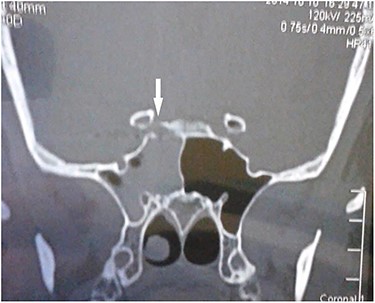

Computed tomography (CT) of the paranasal sinuses and angiography were requested on an urgent basis, which confirmed a diagnosis of pseudoaneurysm in her right CCA, adjacent to retained pellets (Figs 1–4). Also, her hemoglobin dropped from 11.5 to 8.4 gm over a 6-month period. Afterwards, she was referred to the interventional radiology department. She underwent stenting and coiling of her right internal carotid artery after which no further epistaxis happened for an uneventful year of follow-up.

CT scan coronal view showing gun pellets near the right cavernous carotid artery (arrows).